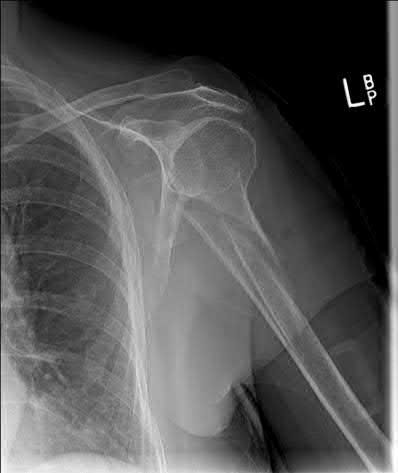

A 62-year-old right-hand-dominant school teacher sustains a mechanical fall at home and presents with right shoulder pain. Plain

radiographs of the right shoulder are pictured in Figures A and B. The patient asks you what she can expect in terms of recovery following this injury. Which of the following is the most appropriate statement?

This patient has a minimally displaced (1-part) proximal humerus fracture involving the humeral neck and greater tuberosity. This injury pattern is most commonly managed nonoperatively with the majority of patients returning to their baseline functional status by 1 year.

Proximal humerus fractures (PHF) can be classified by number of parts (Neer classification), with a part defined as a fracture fragment displaced > 1cm (> 5mm for greater tuberosity) or angulated > 45°. One-part PHF comprise ~80% of all PHF and are treated nonoperatively with a sling and early range of motion (ROM).

Tejwani et al performed a prospective study of 67 patients with 1-part PHF. At 1-year follow up the ASES score and functional status was similar to pre-injury status. However, ROM of the affected shoulder was diminished in both external and internal rotation. Forward flexion was preserved.

Hanson et al prospectively analyzed 160 patients with PHF of all types (1-4 parts and head-splitting) managed nonoperatively. At 1-year follow up, 93% showed solid union. Constant and DASH scores improved steadily over time but were still lower compared to the contralateral extremity. Of employed patients, 97.6% returned to work with a median time off of 10 weeks and no difference between manual and nonmanual workers.

Figures A and B are the AP and axillary radiographs of the right shoulder, respectively, demonstrating a 1-part PHF involving the humeral neck and greater tuberosity.